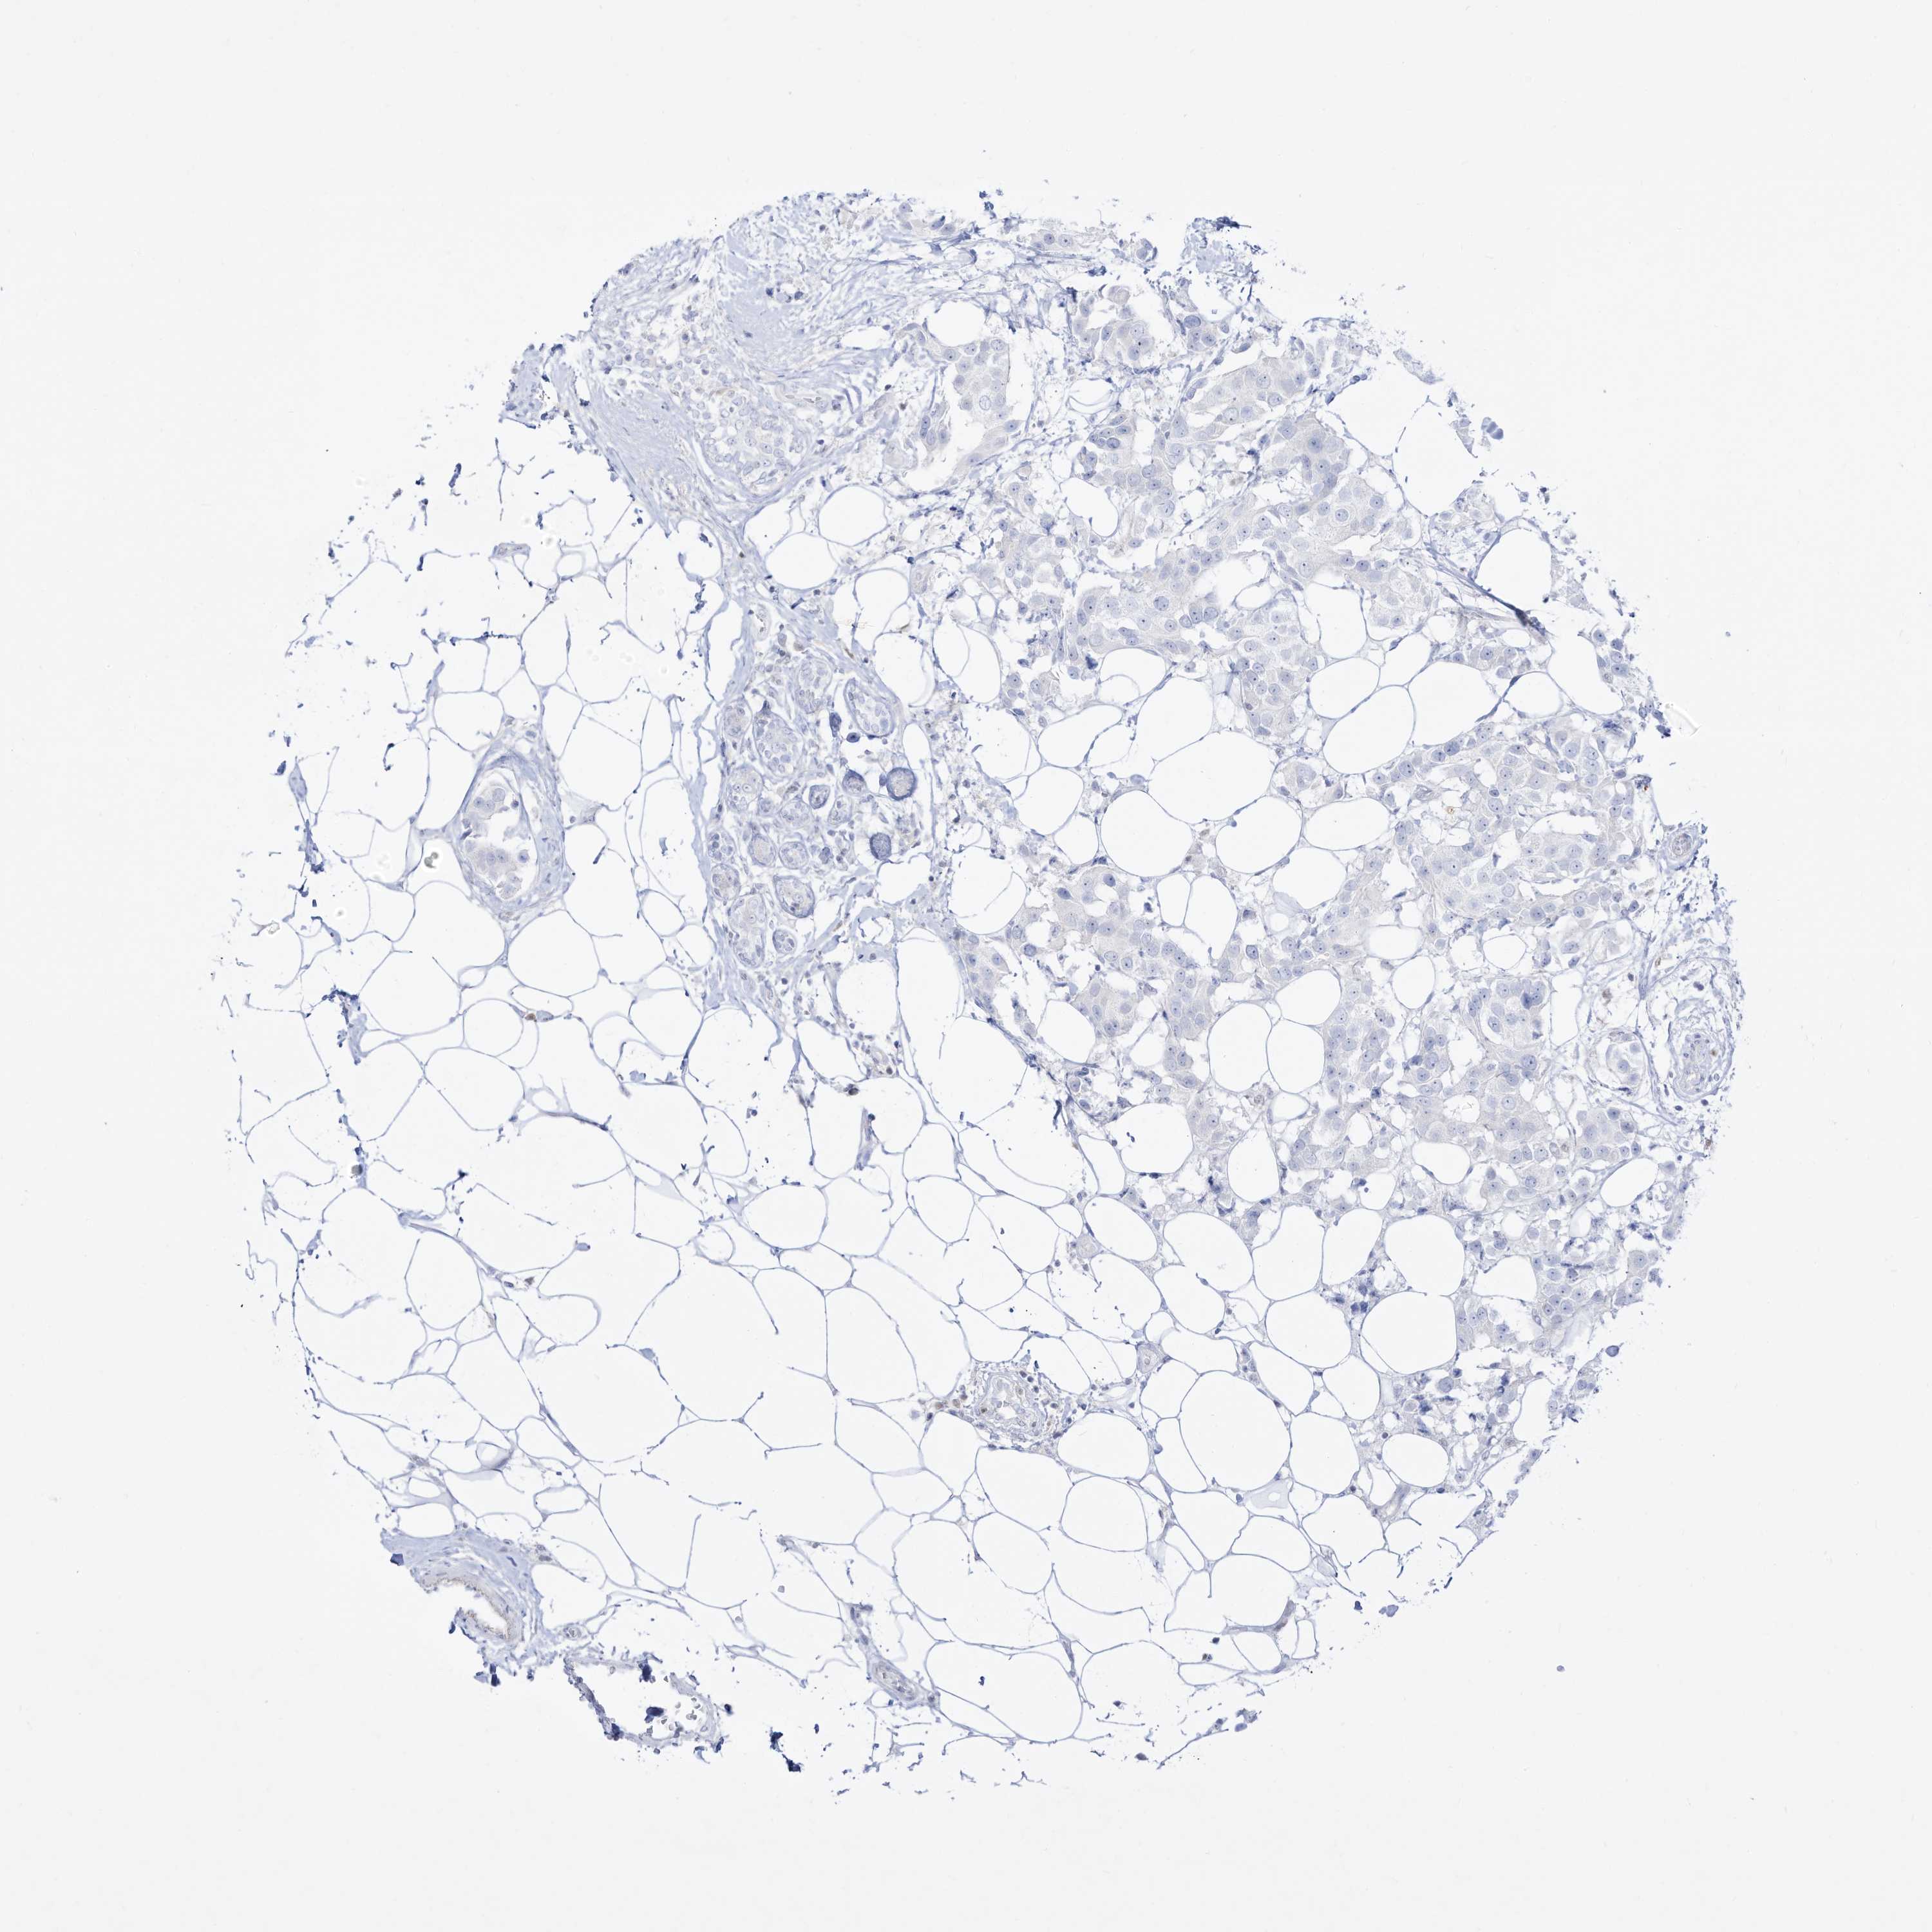

BRCA TCGA BRCA VALIDATION PROTEIN EXPRESSION

ANTIBODIES

AND

VALIDATION